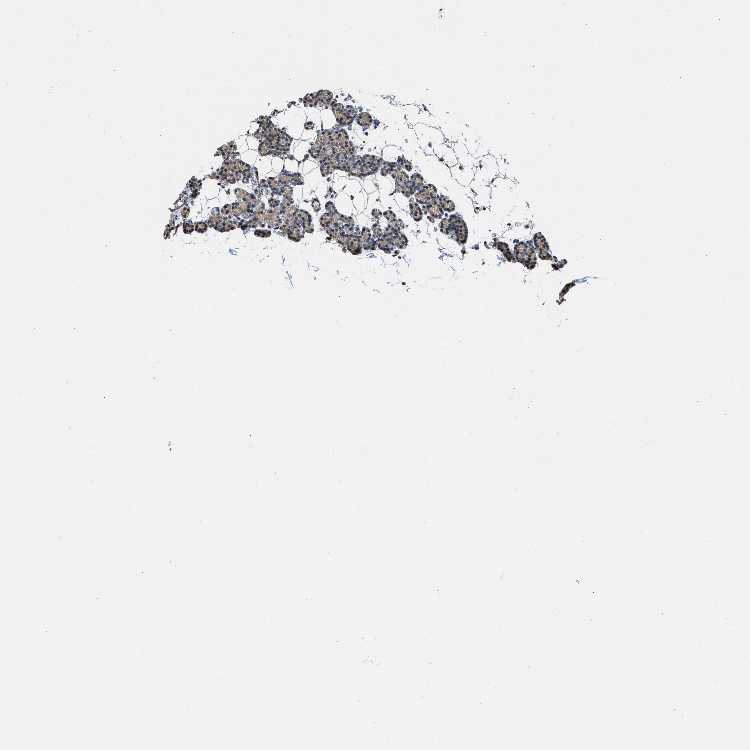

TISSUE PRIMARY DATA PARATHYROID GLAND Show tissue menu

PARATHYROID GLAND - Antibody stainingi

Antibody staining in the annotated cell types in the current human tissue is reported as not detected, low, medium, or high, based on conventional immunohistochemistry profiling in selected tissues. This score is based on the combination of the staining intensity and fraction of stained cells.

Each image is clickable and will lead to virtual microscopy that enables deeper exploration of all samples and also displays staining intensity scores, fraction scores and subcellular localization as well as patient and tissue information for each sample.

Antibody HPA015269Antibody HPA018123

Glandular cells Not detectedLow